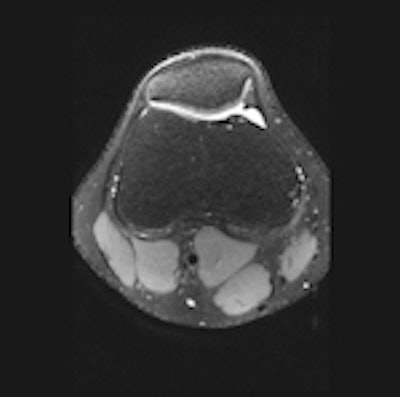

3D SPACE sequence performed at 3 tesla in a 21-year-old man. All scans are 1-mm multiplanar reformatted images in the sagittal (left), axial (middle), and coronal (right) plane. The patient had no abnormalities at arthroscopy. This case illustrates that all relevant structures (menisci, ligaments, and cartilage) can be visualized well using this sequence with good contrast-to-noise ratio between cartilage/meniscus and synovial fluid. All images courtesy of Dr. Pieter Van Dyck.Because uncertainty remains as to whether a single 3D TSE acquisition can replace the multiple conventional 2D acquisitions, studies are needed to determine the diagnostic usefulness of 3D TSE in future knee MR protocols at 3 tesla, Van Dyck and colleagues wrote in an article published online on 26 October by Insights into Imaging. The purpose of their retrospective study was to assess the diagnostic performance of the 3D TSE SPACE sequence, as compared with routine 2D TSE sequences, for evaluating the menisci, anterior cruciate ligament (ACL), and cartilage of the knee joint in symptomatic patients at 3 tesla.

The 3D protocol consisted of a single 3D TSE acquisition in the sagittal plane with the SPACE sequence. The SPACE isotropic source data were postprocessed on a workstation (Leonardo, Siemens Healthcare) to create sagittal, coronal, and axial multiplanar reformatted (MPR) images with 1-mm slice thickness. Readers were free to use volumetric data to create MPRs in any orientation and slice thickness, they stated.